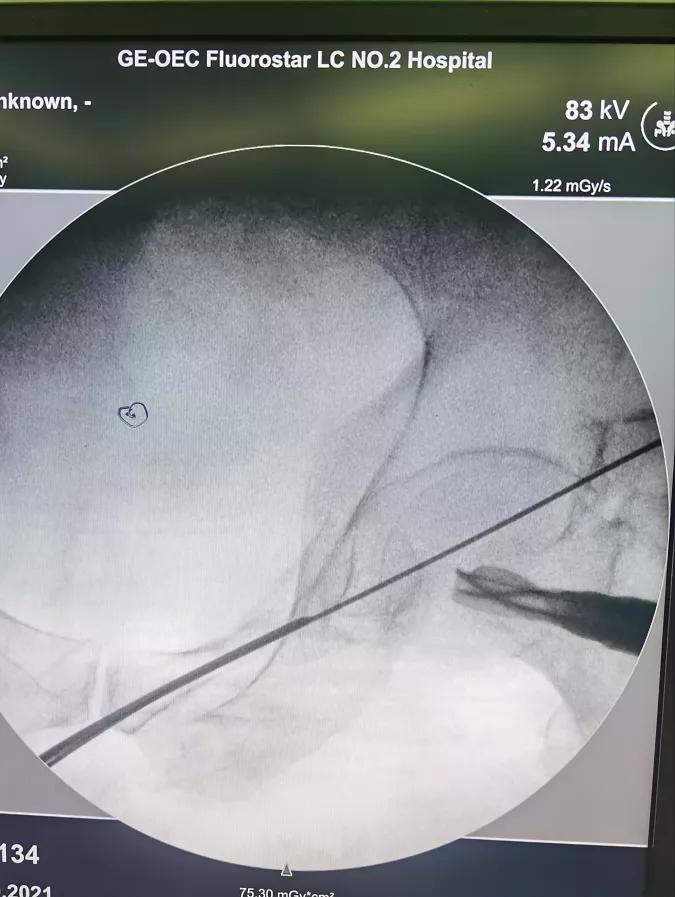

术中影像